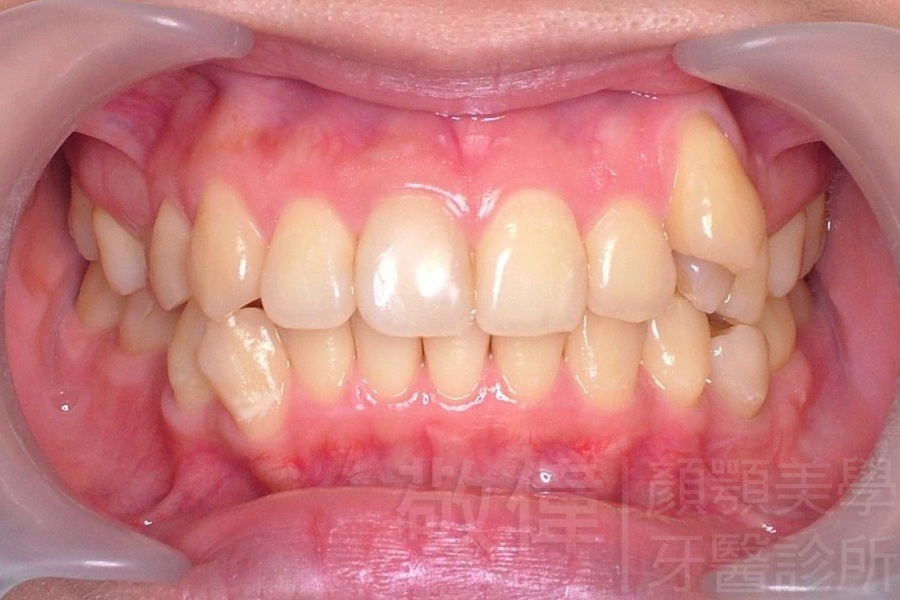

齒顏矯正/上顎暴牙且牙齒極度混亂

矯正前-右   矯正前-正   矯正前-左

矯正後-右   矯正後-正   矯正後-左

<個案說明>

上顎暴牙且牙齒極度混亂,經由矯正之後,臉型大幅度改善,牙齒的排列更加的整齊健康。相較於之前眼神充滿精神,自信心展現無遺。